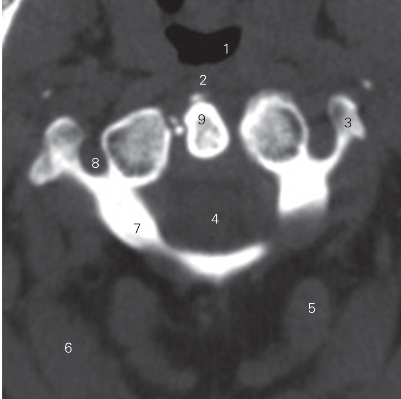

图1-1 经齿突的横断层CT图像(骨窗)

1 喉咽 laryngopharynx 2 咽下缩肌 inferior constrictor of pharynx

3 横突 transverse process 4 颈髓 cervical cord

5 多裂肌 multifidus muscle 6 颈夹肌 splenius cervicis

7 寰椎 atlas 8 横突孔 transverse foramen

9 齿突 odontoid process